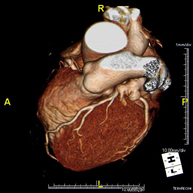

L'angio TC Cardíac o Coronariografia no invasiva és una prova diagnòstica que consisteix en l'estudi de les artèries del cor o artèries coronàries mitjançant l'ús d'un equip TC Multidetector d'última generació i de contrast iodat, i l'obtenció d'imatges bi i tridimensionals. El TC Multidetector o TCMD permet una adquisició d'imatges tan ràpida que es poden valorar les artèries coronàries amb alta precisió anatòmica: estrenyiment o estenosi, calcificacions, variants anatòmiques, etc. ja que gràcies a la seva rapidesa evita l'artefacte que provoca el moviment constant del cor (triga menys de deu segons en adquirir unes 1000 imatges). La informació obtinguda precisa un tractament en estacions de treball amb programes especialitzats en la reconstrucció de les artèries coronàries que permeten valorar el nombre, la localització i les característiques de lesions. Tota aquesta informació s'obté de manera no invasiva: només es requereix la punció d'una vena perifèrica (en el braç). És necessari que la freqüència cardíaca no superi els 75 batecs per minut per això alguns pacients hauran de realitzar un tractament previ amb un fàrmac betabloquejant. - PAAF (punció) de tòrax guiada per TC

The Coronary CT angiography or non-invasive Coronarography is a diagnostic test to examine arteries of the heart, or coronary arteries, using state-of-the-art MDCT equipment (64 slices or rows of detectors) and an iodinated contrast agent to obtain two- and three-dimensional images. 64-slice multidetector computed tomography (MDCT) entails high-speed imaging that is beneficial in assessing coronary arteries with high anatomical precision, particularly in evaluating narrowing or stenosis, calcifications, anatomical variants, etc., as its speed prevents the artefact caused by the constant movement of the heart (1,000 images can be obtained in less than 10 seconds). The information obtained requires processing at workstations equipped with specialised software capable of reconstructing the coronary arteries, thereby enabling an assessment to be made of the number, location and characteristics of the lesions. All this information is obtained non-invasively, involving a simple puncture of a peripheral vein (in the arm). To ensure the heart rate stays below 75 bpm, some patients will need preliminary treatment with beta blockers.